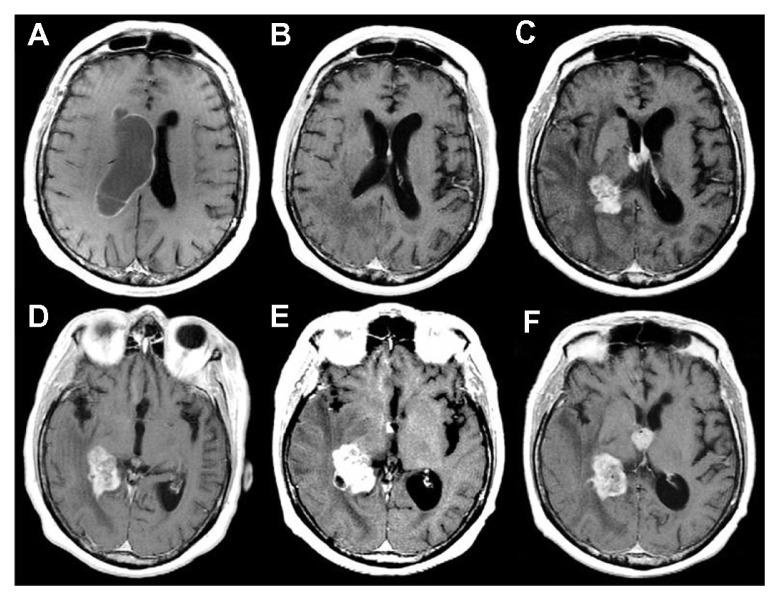

Although various prognostic indices exist for patients with malignant brain tumors, the prognostic significance of the subependymal spread of intracranial tumors is still a matter of debate. In this paper, we report the cases of two intraventricular lesions, a recurrent glioblastoma multiforme (GBM) and a brain metastasis, each successfully treated with a neuroendoscopic approach. Thanks to this minimally invasive approach, we achieved good therapeutic results: we obtained a histological diagnosis; we controlled intracranial hypertension by treating the associated hydrocephalus and, above all, compared with a microsurgical approach, we reduced the risks related to dissection and brain retraction. Moreover, in both cases, neuroendoscopy enabled us to identify an initial, precocious subependymal tumor spreading below the threshold of magnetic resonance imaging (MRI) detection. This finding, undetected in pre-operative MRI scans, was then evident during follow-up neuroimaging studies. In light of these data, a neuroendoscopic approach might play a leading role in better defining the prognosis and optimally tailored management protocols for GBM and brain metastasis.